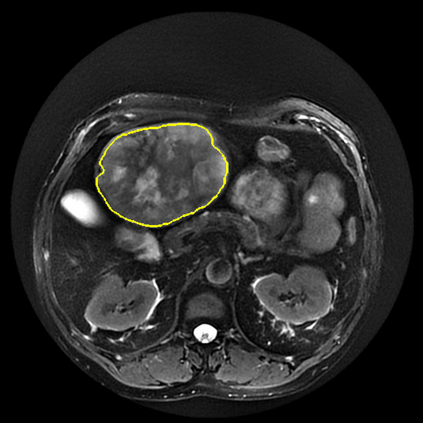

Radiomics uses quantitative medical imaging features to predict clinical outcomes. Currently, in a new clinical application, finding the optimal radiomics method out of the wide range of available options has to be done manually through a heuristic trial-and-error process. In this study we propose a framework for automatically optimizing the construction of radiomics workflows per application. To this end, we formulate radiomics as a modular workflow and include a large collection of common algorithms for each component. To optimize the workflow per application, we employ automated machine learning using a random search and ensembling. We evaluate our method in twelve different clinical applications, resulting in the following area under the curves: 1) liposarcoma (0.83); 2) desmoid-type fibromatosis (0.82); 3) primary liver tumors (0.80); 4) gastrointestinal stromal tumors (0.77); 5) colorectal liver metastases (0.61); 6) melanoma metastases (0.45); 7) hepatocellular carcinoma (0.75); 8) mesenteric fibrosis (0.80); 9) prostate cancer (0.72); 10) glioma (0.71); 11) Alzheimer's disease (0.87); and 12) head and neck cancer (0.84). We show that our framework has a competitive performance compared human experts, outperforms a radiomics baseline, and performs similar or superior to Bayesian optimization and more advanced ensemble approaches. Concluding, our method fully automatically optimizes the construction of radiomics workflows, thereby streamlining the search for radiomics biomarkers in new applications. To facilitate reproducibility and future research, we publicly release six datasets, the software implementation of our framework, and the code to reproduce this study.

翻译:放射科使用定量医学成像特征来预测临床结果。目前,在一个新的临床应用中,通过一个超常试验和高压过程,通过人工操作,从广泛的现有选项中找到最佳放射法。在本研究中,我们提议了一个框架,自动优化每个应用程序的放射工作流程的建设。为此,我们将放射作为模块工作流程,并包括每个部件的大量通用算法。为了优化每个应用程序的工作流程,我们使用随机搜索和聚合的自动机学习方法。我们用12种不同的临床应用来评估我们的方法,结果在曲线下应用的以下领域:1) 脂色瘤(0.83);2) 脱氧型纤维瘤(0.82);3 初级肝脏肿瘤(0.80);4 气肠肿瘤(0.77)、5 彩虹肝脏移植(0.61); 6 脑膜细胞变异常(0.45); 7) 肝细胞变异常(0.8) 脑纤维变异位(0.80); 9) 直径直线型癌症(0.74) 和头型癌症(0.77) 直径研究(10) 。